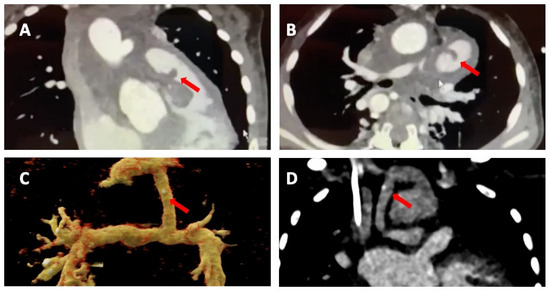

Figure 1. Transthoracic echocardiography of an adult patient with previous Ross procedure for bicuspid aortic valve using a pulmonary homograft. There are large mobile vegetations (max ~18 × 7 mm, (A,B), black arrows) on the pulmonary homograft. Severe pulmonary regurgitation (regurgitant jet originating in the main pulmonary artery, vena contracta 8.5 mm, (C)); no significant stenosis (mean gradient 13 mmHg, peak gradient 26 mmHg, (D)). The findings are consistent with infective endocarditis. Images courtesy of Ms Joane Daradar—Echocardiography Department, Royal Brompton and Harefield Hospitals, London.